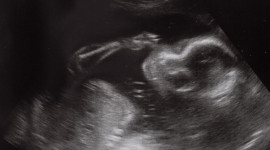

Dziecko, o którym mówiono, że zabiło własną matkę, mogło ją uratować.

Irlandia, rok 2018. Społeczeństwo, o którym mówi się, że jest konserwatywne i prawicowe, wykreśla w drodze referendum tzw. Ósmą poprawkę do konstytucji. Skutek: wprowadzenie aborcji na życzenie. Jedni są zszokowani i nie dowierzają, inni zacierają ręce, że stary scenariusz znowu się sprawdził. Po co przypominam teraz tę historię? By pokazać, w jaki sposób śmierć matki w ciąży może być propagandowo użyteczna.